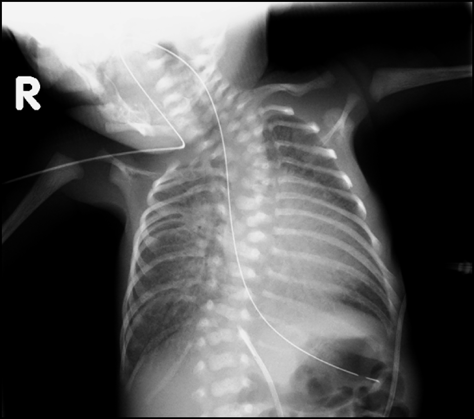

Fig. 2 Schematic diagram, echocardiogram, and fluoroscopic image

a) Schematic diagram of the patient’s anatomy. The four pulmonary veins join a confluence that drains the vertical vein to the left portal vein, ductus venosus and IVC to RA. Vertical vein, left portal vein and ductus venosus form U-shaped curve. b) Echocardiography. White arrow shows ductus venosus measuring 1.1 mm at its short axis and 9.4 mm at its long axis diameter. c) Using the umbilical vein catheter as a landmark, we inserted a 0.014-inch guidewire into the vertical vein.

入院時,心拍数156回/分,血圧66/23 mmHg,呼吸回数46回/分で経皮的酸素飽和度86%(経鼻的持続陽圧呼吸療法PEEP 5 mmHg,FiO2 0.21),胸部聴診で肺雑音なし,心音整,心雑音は聴取しなかった.胸部X線で心胸郭比57%,両側肺血管陰影の増強を認めた(Fig. 1).血液検査で特記すべき異常なし.心臓超音波検査では右房,右室の拡大を認め,左室拡張末期径10.3 mm(正常期待値の76%),左室駆出率68%,心房中隔欠損4.9 mm,圧較差なく右左短絡,左右肺静脈が合流して共通肺静脈腔を形成し,共通肺静脈腔から垂直静脈が左門脈へ還流していた.垂直静脈(vertical vein: VV)は横隔膜を貫通する部位では狭窄なく,垂直静脈の左門脈合流部から静脈管(ductus venosus: DV)にかけてU字型に走行しており(Fig. 2a),同部位で狭窄があり,PVOを認めた(Fig. 2b).血流波形は連続性であり,最大流速1.6 m/s,平均圧較差7 mmHgであった.動脈管は両方向短絡だった.心外疾患として,椎体・右胸郭形成不全,右内反足・右膝拘縮,右腎低形成と診断された.遺伝染色体疾患の精査のため,術後に遺伝染色体科へのコンサルトを行い,染色体検査が行われたが正常核型であり,VACTERL連合と診断された.

カテーテル治療① アプローチおよびバルーンによる前拡張

日齢4(修正33週2日,体重1,109 g),ミダゾラム,フェンタニル,ロクロニウムを用いた静脈麻酔薬による全身麻酔下で経皮的バルーン形成術,血管内ステント留置術を行った.肺出血の懸念があるためヘパリンは使用しなかった.臍静脈からアプロ—チした際,DV, IVCへカテーテルは挿入できるが,VVへの挿入は困難と考え,頸部からアプローチすることにした.右内頸静脈に6 Fr Merit Prelude IDealシース(Merit Medical, South Jordan, UT, USA)を留置し,4 Frマルチパーパスカテーテル(フォルテ グロウ メディカル株式会社,栃木,日本),先端転向型マイクロカテーテルである,2.9 Frレオニスムーバ®(SBカワスミ株式会社,神奈川,日本)を用いて,臍静脈カテーテルを目印にすることで0.014インチGTワイヤー®アングル(テルモ株式会社,東京,日本)をVVへ挿入できた(Fig. 2c).ガイドワイヤーの挿入が困難な場合は臍静脈カテーテルから血管造影し,臍静脈からスネアを挿入し内頸静脈から挿入したガイドワイヤーを把持して静脈管を通過させる予定であった.2.9 Frレオニスムーバ®はVVとDVがU字型に吻合している部位を通過しなかったため,1.9 Fr Carnelian® MARVEL(東海メディカルプロダクツ株式会社,愛知,日本)を使用することで,2.9 Frレオニスムーバを挿入できた.PVO解除前のカテーテル挿入,血管造影はPVO悪化による肺出血の懸念があったため,圧測定と血管造影は行わず直ちに経皮的バルーン形成術を行った.0.014インチBalance®ガイドワイヤー(Abbott, Pylmouth, MN, USA)を左肺静脈へ挿入後,血管拡張用バルーンTrek®(Abbott, Pylmouth, MN, USA)3 mm×15 mm, 4 mm×15 mmでVV,VVとDVの吻合部,DVの3か所をいずれも16気圧で前拡張した.血管拡張用バルーンSterling®(Boston Scientific, Marlborough, MA, USA)5 mm×20 mmを用い,10気圧で拡張した(Fig. 3a).VVで造影し,最狭窄部径4.7 mmと狭窄が残存していたため,ステント留置術の方針とした(Fig. 3b).